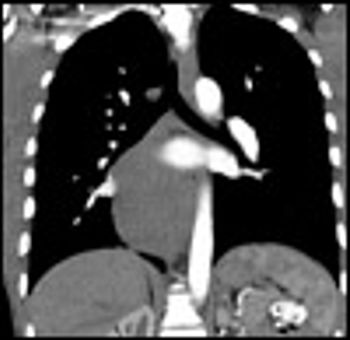

A 24-year-old man with an unremarkable medical history presented to the emergency department with abdominal pain and hematemesis of 3 days' duration. His symptoms were postprandial, and each episode yielded up to half a cup of blood without clots. He denied using NSAIDs or alcohol. He had had an episode of hematemesis 2 years earlier that resolved spontaneously, for which he had not sought treatment. His vital signs were normal, and his physical examination was notable only for moderate epigastric tenderness without rebound or guarding.